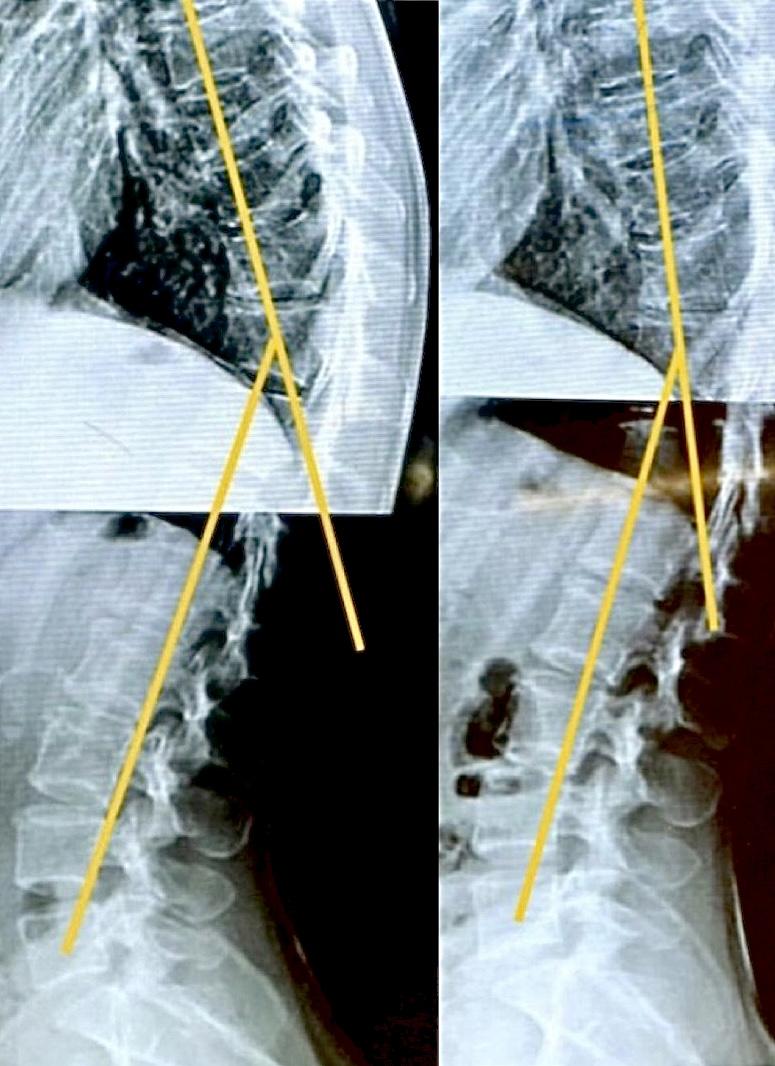

小学生の改善例(男の子)

小学生の男の子、学校の検診にて「側彎症の疑いあり」と告げられ来院。元々親御様が当院にてケアを受けられていたこともあり、カイロプラクティックの重要性や必要性を理解されていたことからお子様のケアも担当させていただくことになりました。側彎症とストレートネックの改善と共に重度の卵アレルギーなども改善されたそうです。現在も健康管理のためご家族全員で定期的にケアを受けられています。

※これは個人の感想と画像の結果であり施術の効果を保障するものではありません。また効果には個人差があります。